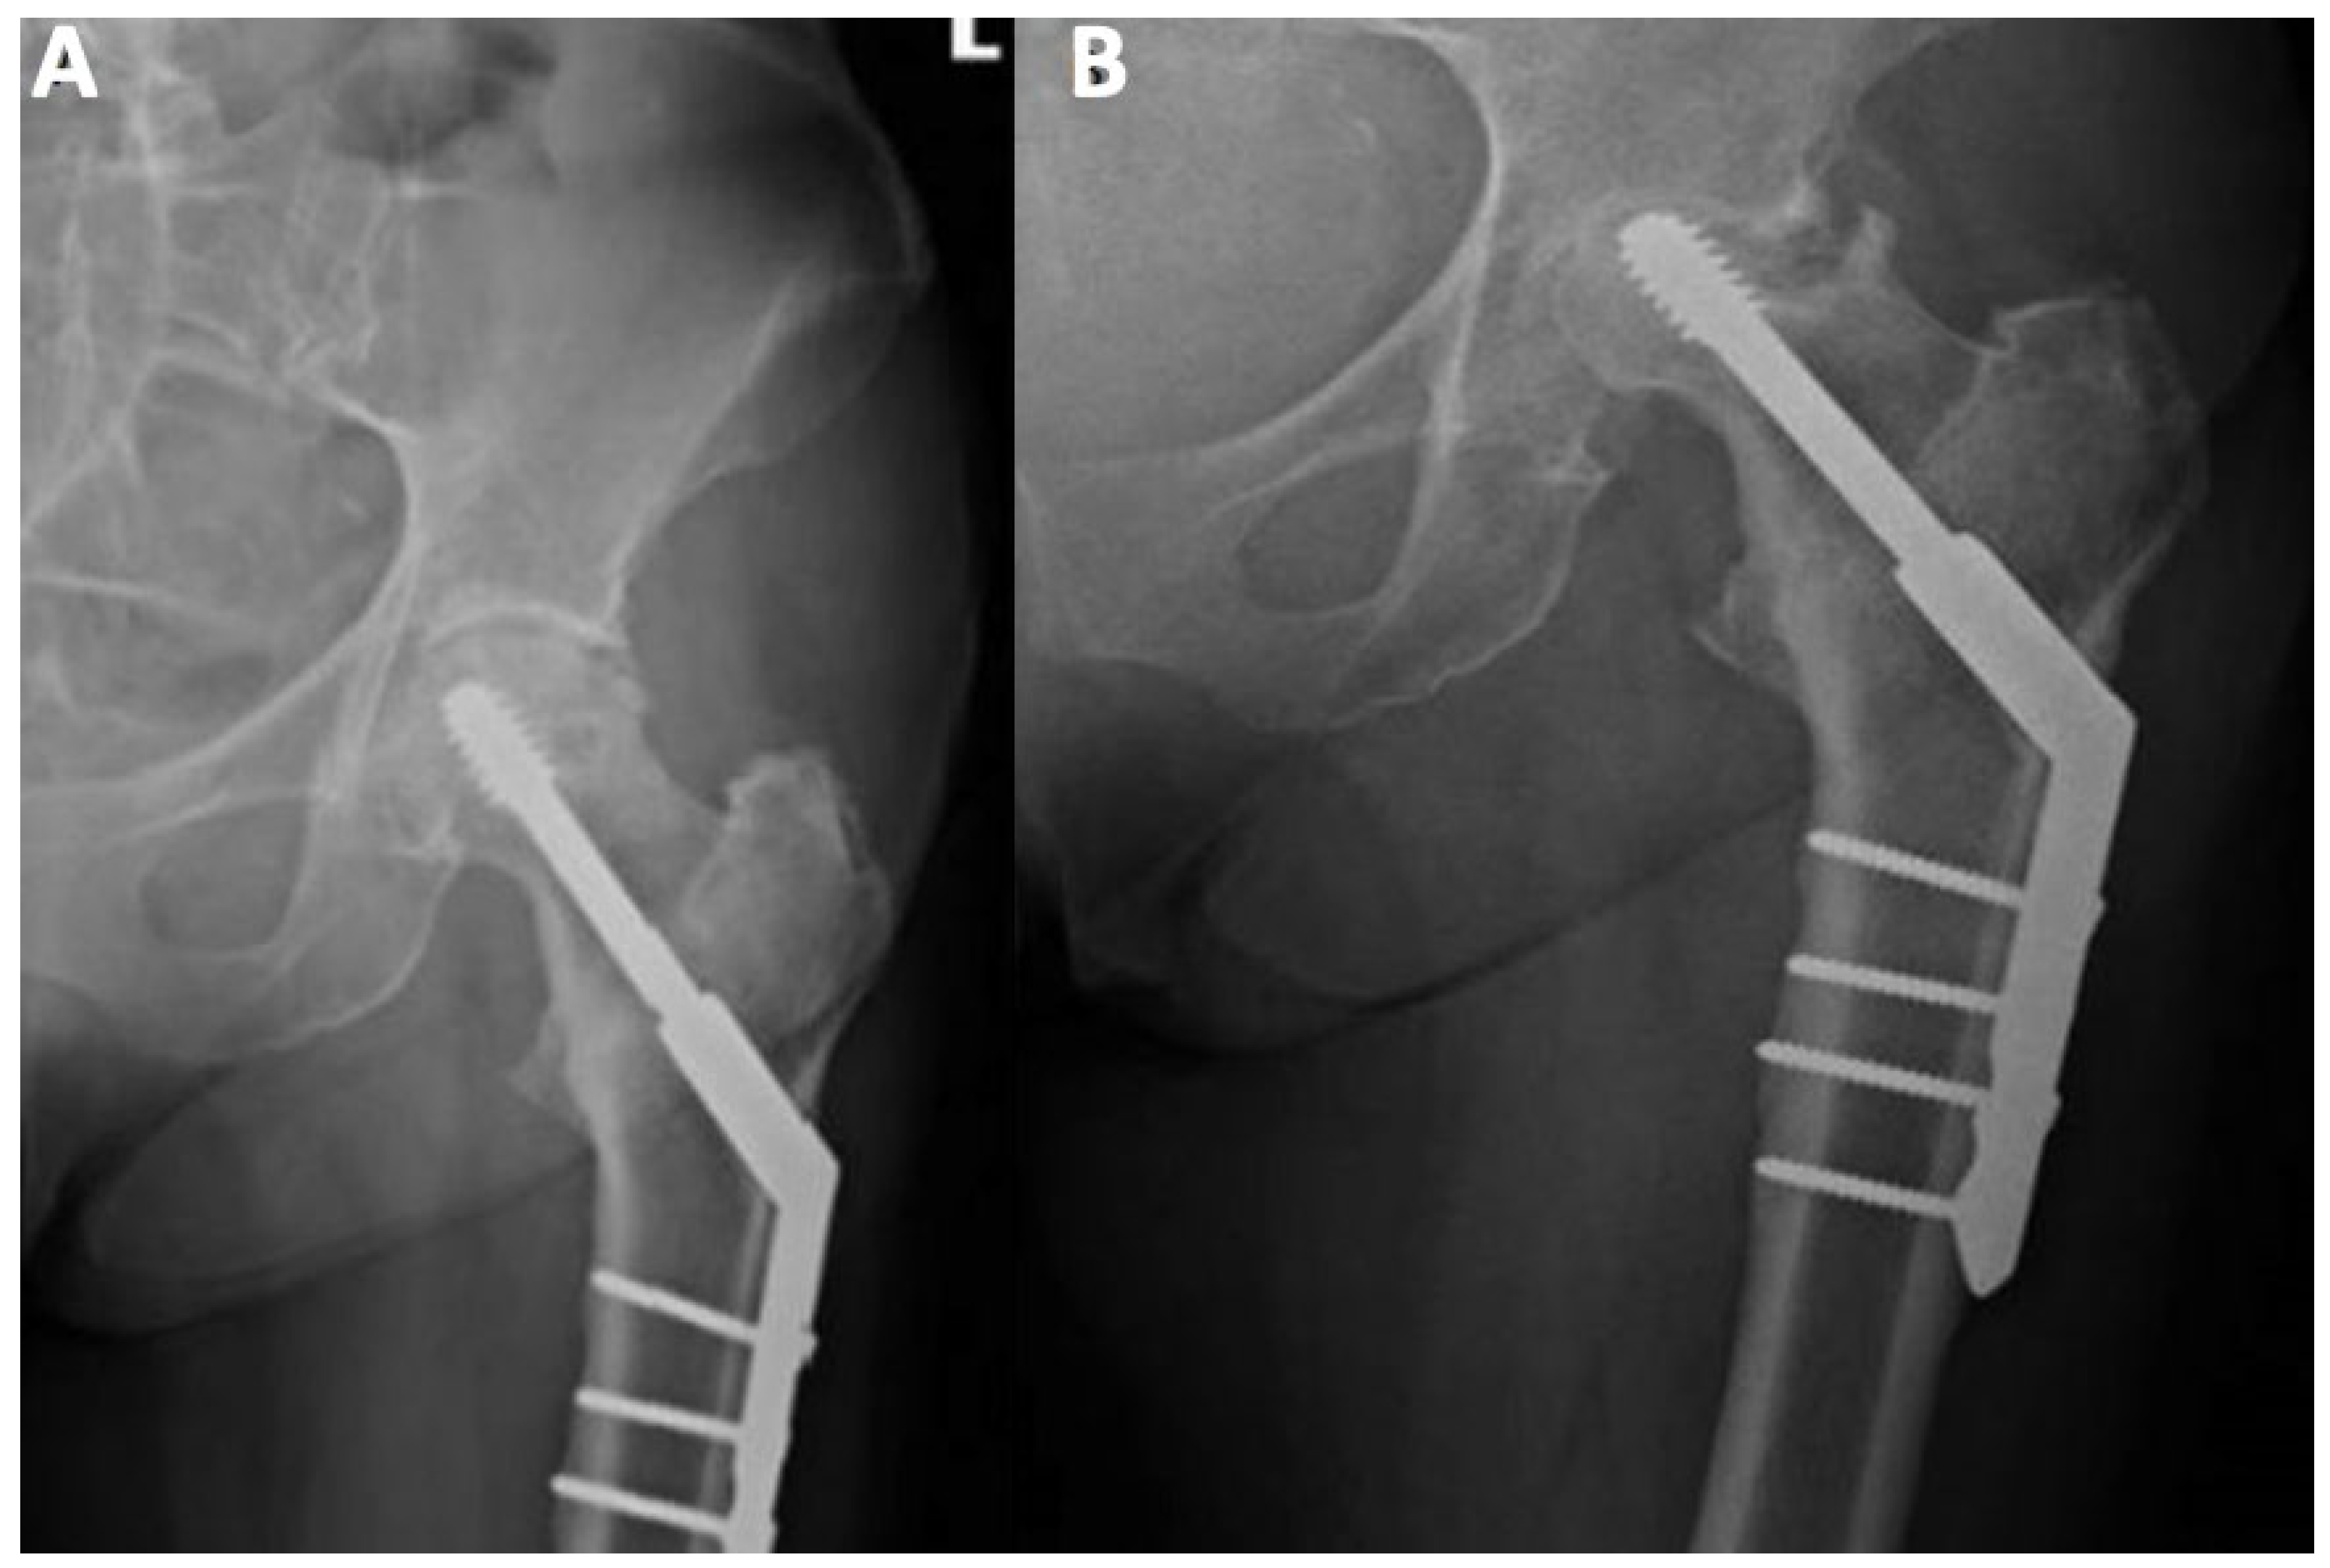

3. Clinical and Radiographic Examination of the AVN

MRI is the gold standard for osteonecrosis diagnosis and allows differentiating AVN from other diagnoses that may mimic it, such as bone bruises or transitioned osteopenia [1,9]. MRI allows for early AVN diagnosis and may help identify patients at risk of femoral head fracture. Identification of bone marrow edema in the proximal femur and joint effusion are critical prognostic factors [3]. T1-weighted images show a limited subchondral linear-shaped low signal intensity, while T2 demonstrates a double-line sign [44]. However, MRI cannot be used after fracture fixation with metallic implants, limiting its utility, especially in patients who develop bone ischemia following surgical procedure [18].

Figure 3. The posteroanterior view shows a right (R) AVN of the femoral head (T1-weighted).